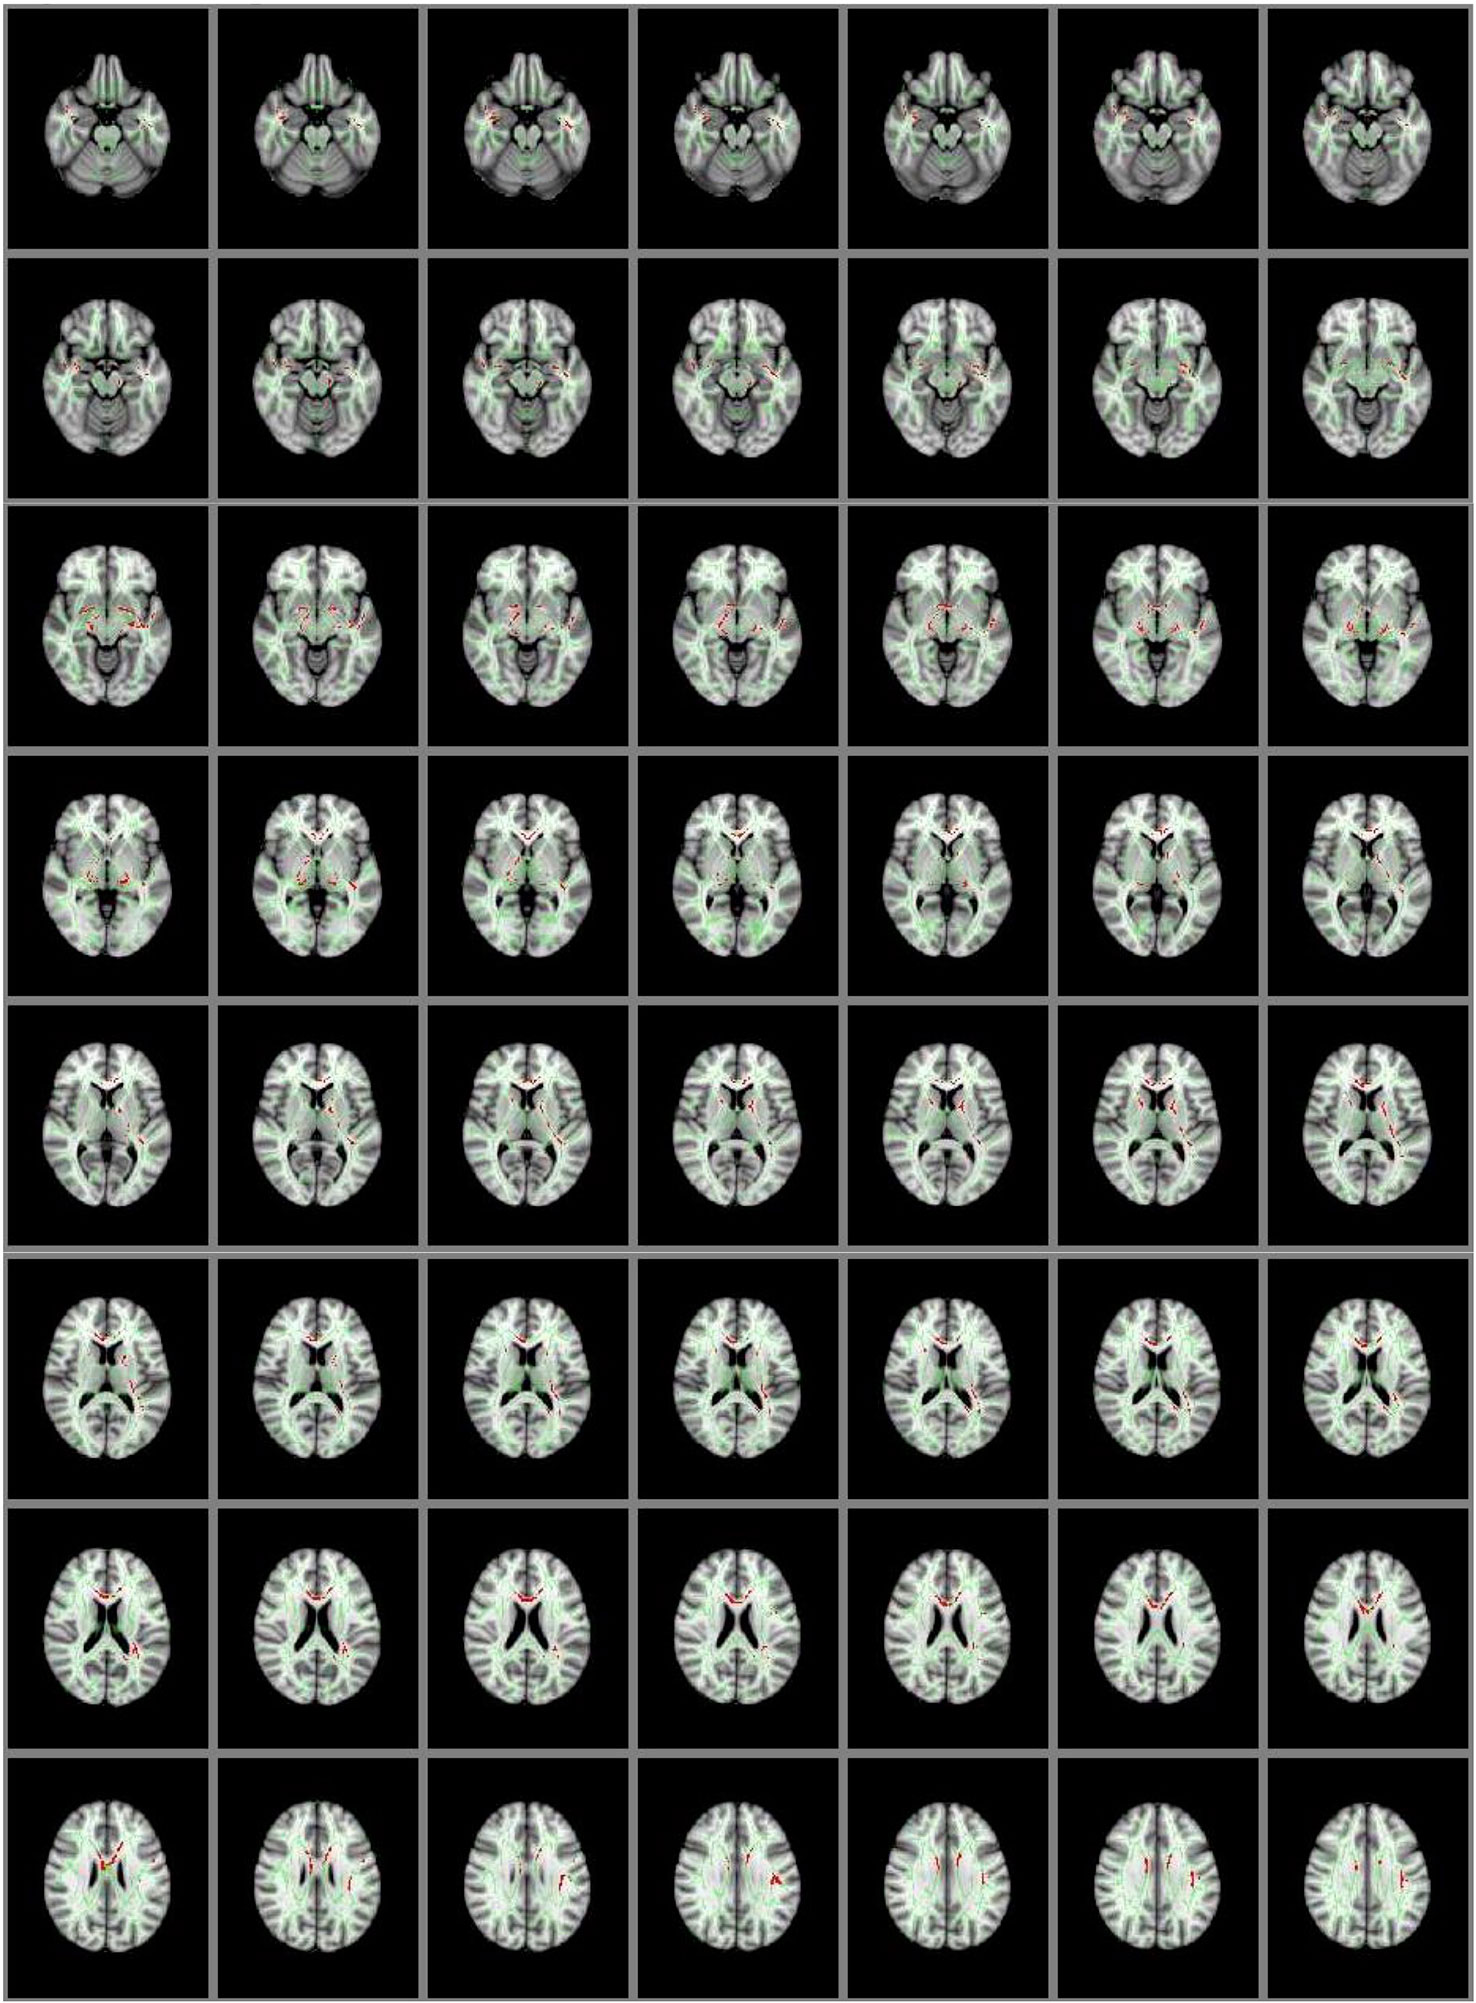

The whole brain group comparison analyses revealed several areas that showed significantly lower GFA in the NSSI group when compared to the HC group at a corrected p < .01 (corrected through permutation testing within TFCE as described in 39). In addition to the cingulum and uncinate fasciculus as predicted, these areas also included bilateral superior and inferior longitudinal fasciculi, anterior thalamic radiation, callosal body, and corticospinal tract. Figure 2 depicts the locations of these group differences.

Figure 2 Group Differences in GFA: Controls > NSSI. White matter tracts in red show where controls have significantly greater GFA than NSSI. This is overlaid on the mean GFA skeleton (light green). Findings were significant at p < .01.